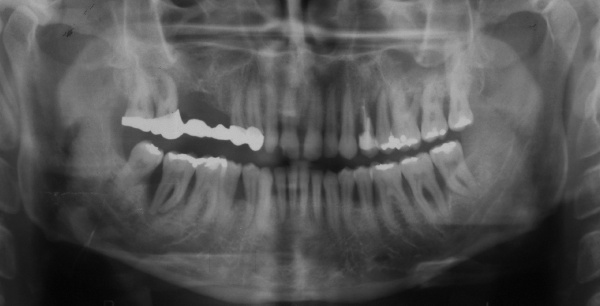

Der Erstbefund vom 20.08.1998 zeigte eine lokalisiert entzündliche marginale Gingiva mit Blutungsneigung auf Sondierung (SBI 32 %) vorrangig in regio 17, 11, 21, 24, 27, 36, 37, 41, 46. Austritt von Pus aus der Tasche an 22. Die Sondiertiefen waren durchweg erhöht, an einzelnen Parodontien konnten bis zu 12 mm sondiert werden (s. Abb. 12). Generalisiert weiche Beläge (API 46 %), harte Beläge in der UK-Front. An 41 singuläre parodontale Rezession und Zahnlockerung des Grades II, hier auch sehr schmale keratinisierte Gingiva. Mobilitätstest und Blanchingtest positiv. Der Röntgenbefund der Panoramaschichtaufnahme vom 11.08.1999 (s. Abb. 13) zeigt einen generalisierten horizontalen Knochenabbau mit vertikalen Einbrüchen in regio 17, 24, 25, 26, 36, 41 und 47. Wurzelfüllung an 36. Konkremente sichtbar. 18 elongiert. 38 und 48 halbretiniert mit Aufhellung distal.